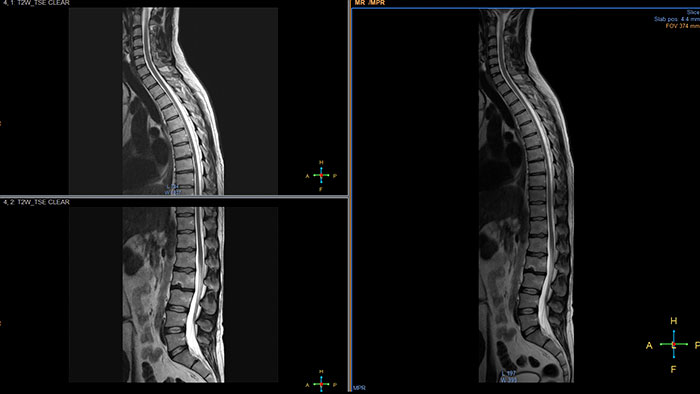

Advanced Diffusion Analysis (ADA)

MR Advanced Diffusion Analysis

Computed diffusion weighted images at a b-value of choice

The application is intended to view, process and analyze MRI Diffusion Weighted Images. It calculates and displays cDWI at a

b-value of choice (from 0 to 5,000 s/mm2) and provides advanced supportive analysis and visualization tools of diffusion MRI images and parametric maps.

• Presents a default diffusion analysis model based on the available original DWI images as well as a selection of alternative models including monoexponential, biexponential, simplified IVIM, and kurtosis.

• A ‘goodness of fit’ value and fitted curve show the fitting quality of the selected model.

• Provides parametric maps of perfusion fraction (f), pseudo diffusivity (D*), Diffusivity (D) and Kurtosis (K).